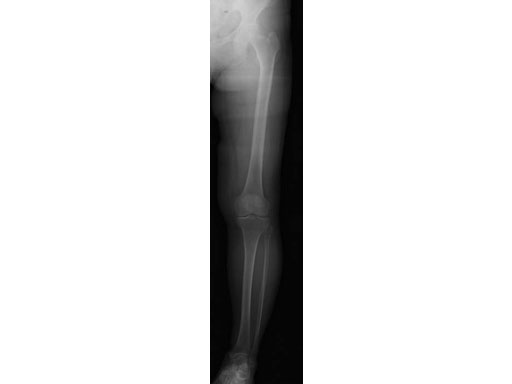

65-year-old female. Osteoarthritic patient complaining of medial knee pain of her left knee.

Case provided by Takeshi Sawaguchi, Toyama, JP